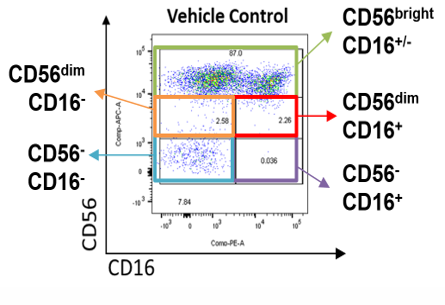

A

Fig 2: (A) FACS gating strategy of different NK cells subsets was used to quantify the proliferation of NK post exposure to Test Compounds. (B) NK specific killing of K562 cells. Test Compound primed NK cells were incubated with K562 cells at different E:T ratio from 0.5:1 to 16:1 for 4 hours (in triplicates) at 37°C in a 95% humidified chamber with 5% CO2. The cytotoxicity of K562 (% Specific lysis) was determined using CTG assay.